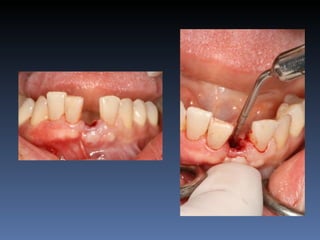

BOX 4

Ville Victorazzo Carmo

Idade – 20 anos

Sexo – Masculino

Raça – Caucasiana

ASA – I

Data- 27-04-2012

Diagnóstico: Desdentado da zona 2.1,

pré-regenerada.

Plano de tratamento: Instalação de implante endo-

ósseos ( 2.1 ) para reabilitação protética fixa.